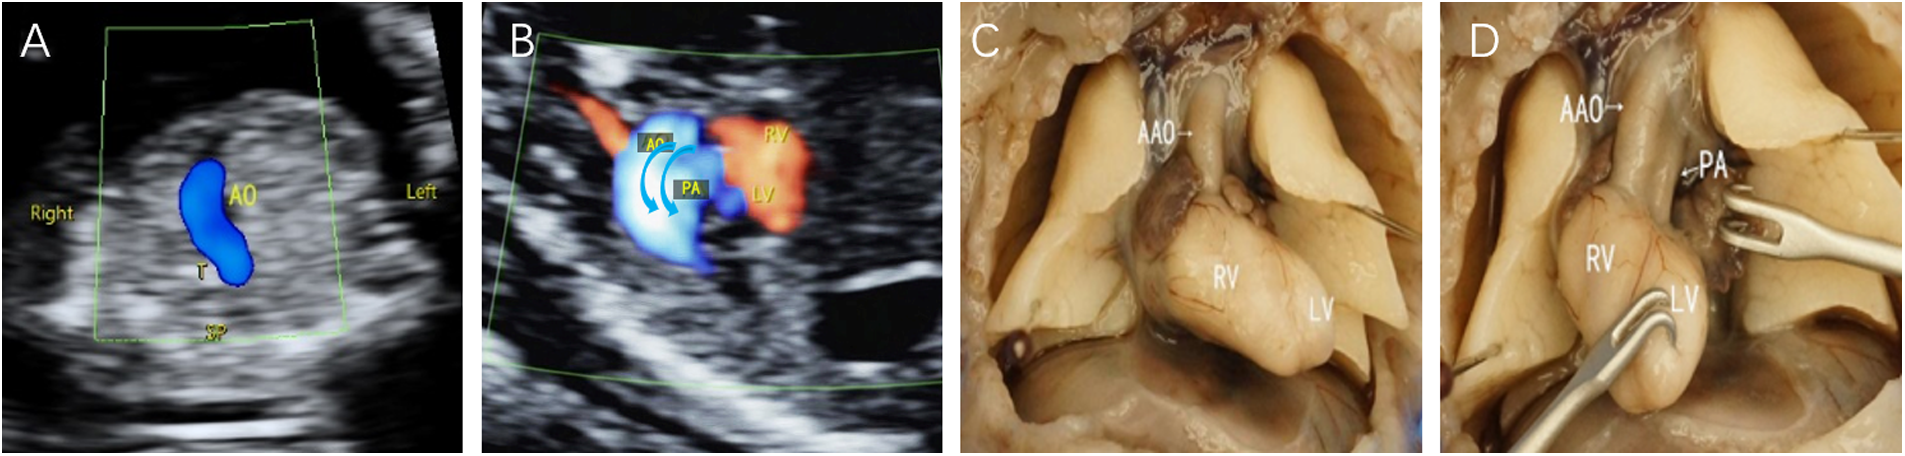

Figure 1

Fetal D-TGA patients were assessed via echocardiography at 13 weeks and 2 days. (A) 3VT view showing only one large artery running anteriorly to the right in a “dart-like” pattern. (B) Oblique thoracic view showing the juxtaposition of large vessels. (C,D) Microscopic dissection of the heart: the two large arteries are aligned in parallel, with the aorta located anteriorly to the right of the right ventricle; the pulmonary artery is located posteriorly to the left of the left ventricle.